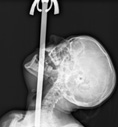

Una tarda, a la facultat, en una classe sobre el funcionament de la gola que fins aleshores era una mica avorrida, el professor va dir: «Si s’hi encalla alguna cosa, s’hi pot obrir un pas tirant endavant l’os de la barbeta.» Per il·lustrar-ho, ens va ensenyar una radiografia d’una faquir empassant-se una espasa.

Tres anys després, era un metge en pràctiques treballant en una guàrdia hospitalària de veritat. Un dels meus primers pacients va ser una senyora gran amb una tos persistent. Sempre preguntava als meus pacients a què es dedicaven per si podia ser rellevant per al cas, i va resultar que la dona es dedicava a empassar-se espases. Imagineu-vos la meva sorpresa quan vaig descobrir que era ni més ni menys que la mateixa faquir de la radiografia! I imagineu-vos també quina cara em va quedar quan, després d’explicar-li els meus intents frustrats d’empassar-me una canya de pescar, em va dir: «Però doctor, ¿que no sap que la gola és plana? Només t’hi pots ficar objectes plans. Per això fem servir una espasa.»